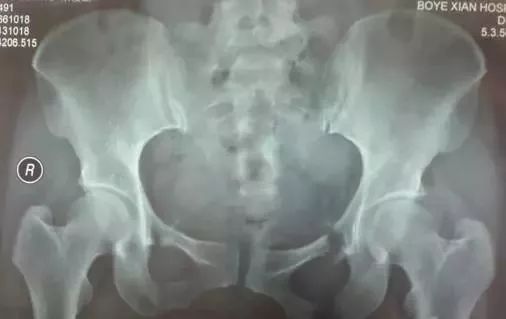

1、骨盆基本划线

a、Calve线(卡尔维氏线):髂骨外缘与股骨颈外缘所连成的弧线,能反应股骨头与髋臼的关系及髋臼上缘的完整性。

b、臼顶线 连接髋臼上缘的弧线,与泪滴外侧缘相续(黄线),代表髋臼的负重区。

c、shenton线(沈通氏线)耻骨下缘与股骨颈内侧缘所连成的弧线,正常时此线连续光滑,能反应股骨头与髋臼的关系。

d、髂坐线 连接髂骨内缘与坐骨内缘的曲线,正常时此线为连续光滑曲线,能反应四边体的完整性。

e、髂骶线 连接髂骨弓状线与骶骨岬的弧线,代表骨盆后环完整性。

f、髂耻线 连接双侧髂骨内缘与耻骨上缘的弧线,代表骨盆前环的完整性。

g、泪滴线(U形线)连接泪滴周围所形成的曲线,代表髋臼的内缘,一般用于髋臼假体深度的评价,髋臼内缘紧邻泪滴线的外缘。

h、前唇线 髋臼前缘所连成的弧线,代表髋臼前壁的完整性。

j、后唇线 髂骨外缘与髋臼后缘所连成的弧线,代表髋臼后壁的完整性。

K、闭孔内缘线 沿闭孔内缘所连成的弧线,正常情况下双侧闭孔对称,当骨盆旋转时可发生改变。

2、基本线标

⑴成人骨盆基本线标

a 、连接双侧髋臼顶端的连线,代表髋臼的上界及负重区。

b 、连接双侧大转子尖顶点的直线,正常通过双侧股骨头中心,一般用于股骨头置换术后股骨头高度的评价。

c 、连接双侧泪滴尖端的直线,代表双侧髋臼的最下缘,一般用于人工关节置换对髋臼假体位置的评价,正常时髋臼假体的内下缘紧贴此线的上缘。

d 、连接双侧坐骨结节下缘所成的直线,代表骨性骨盆的最下缘。

e 、连接双侧小转子下缘所成的直线,代表股骨近端最下缘。

f 、坐骨内缘与髂骨内缘的双切线,也称谓kohler线(科勒氏线),代表髋臼的内侧界,一般用于髋关节置换中假体深度的评价,髋臼陷入症或髋关节置换骨质磨锉过深时髋臼突至此线内侧。

g 、经过耻骨联合的直线,为骨盆的对称轴。

h、双侧髂骨最高点的连线,代表骨盆的最高点。

正常情况下,骨盆的六条水平线相互平行,且与经耻骨联合线垂直,当六条水平线出现不平行情况时,表示存在骨折错位或骨盆与髋臼的发育不良。